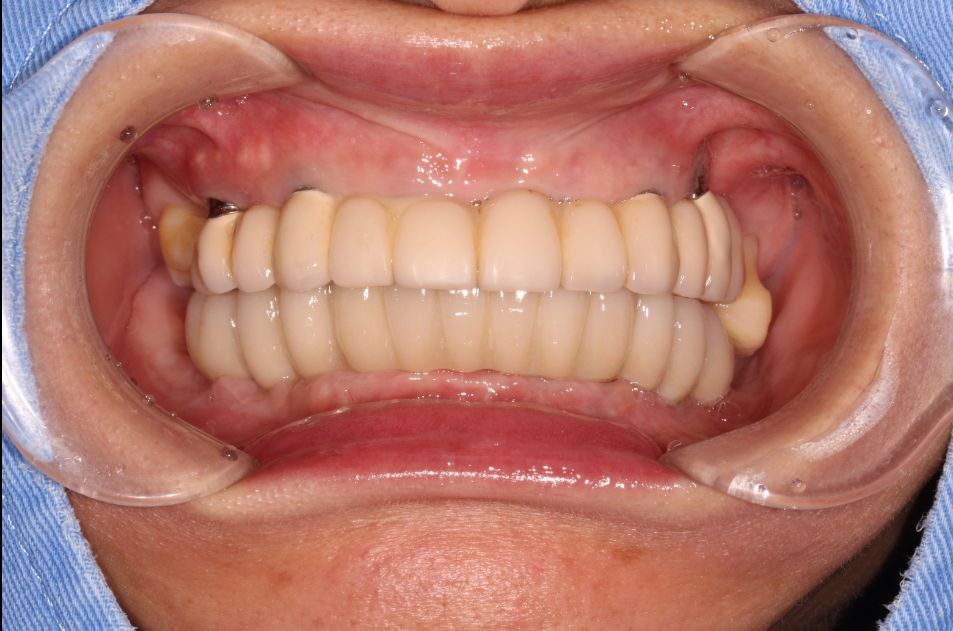

这是一位今天种植牙复诊患者的牙齿的,早期因为牙齿缺失和牙齿松动,严重影响美观,更影响了她的饮食,15年前我为她种了上半口,一直用得很好!但下合的牙因重度牙周病引起牙齿松动和脱落,今年我又为她种了下半口;经过采用种植牙的方式,使得她的牙齿重换新生,患者说:“戴上牙以后什么都能吃,体重还重了许多,很庆幸当时选择种牙这个选择”。

感谢这位患者的肯定和信任!!

戴牙图片